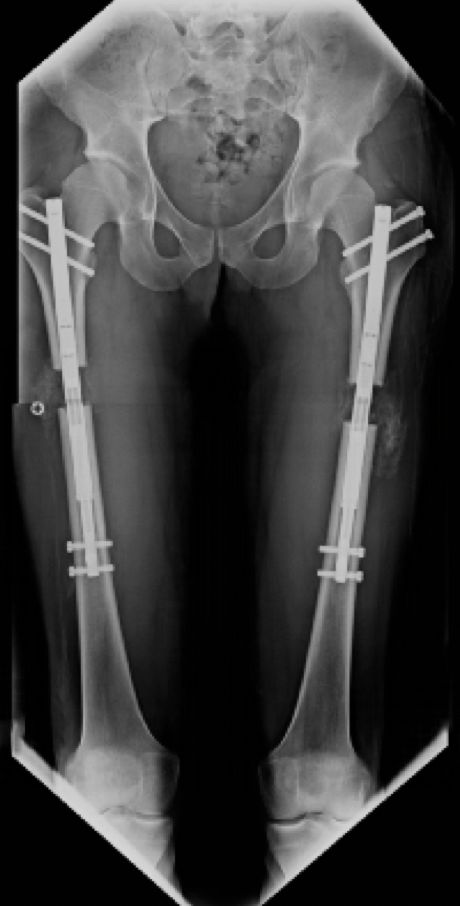

Jestem chirurgiem specjalizującym się w zaawansowanych rekonstrukcjach stawów oraz wydłużaniu kończyn dolnych (limb lengthening and reconstruction surgery). Kompleksowo opiekuję się osobami z problemami o podłożu ortopedycznym oraz neurologicznym, szczególnie dzieci z wadami wrodzonymi i schorzeniami nerwowo-mięśniowymi. Dzięki wieloletniemu doświadczeniu w nowoczesnych technikach rekonstrukcyjnych znacząco udoskonaliłem metody chirurgicznego leczenia dzieci z problemami neurologicznymi, otwierając przed nimi nowe możliwości poprawy funkcjonalności oraz jakości życia. Specjalizujemy się w jednoczasowych wielopoziomowych rekonstrukcjach kończyn (SEMLS) oraz kompleksowych rekonstrukcjach stawów biodrowych, łącząc sprawdzone techniki operacyjne z innowacyjnymi rozwiązaniami. Oprócz leczenia operacyjnego, koordynuje leczenie zachowawcze, obejmujące wielopoziomowe podania toksyny botulinowej (BTX) oraz minimalnie inwazyjne procedury, takie jak SPML (Selective Percutaneous Myofascial Lengthening) czy PERCS (Percutaneous Muscle Lengthening). Każdy pacjent otrzymuje indywidualnie opracowany program terapeutyczny, którego celem jest osiągnięcie najlepszych efektów przy minimalnym obciążeniu. Opiekuję się również pacjentami dorosłymi wymagającymi endopiotezoplastyki stawów oraz ratowaniem kończyn przed amputacją z powodu aktywnej lub przewlekłej infekcji W mojej pracy kluczowe jest podejście holistyczne, które łączy zaawansowane techniki chirurgiczne z terapią zachowawczą, aby zapewnić pacjentom kompleksową opiekę oraz trwałe efekty leczenia. Powierzenie nam zdrowia pacjentów jest dla nas ogromną odpowiedzialnością, a jednocześnie najwyższym zaszczytem. Zakres mojej specjalizacji obejmuje leczenie: 1. Wady wrodzone i rozwojowe kończyn: Hemimelia strzałkowa, niedorozwój kości udowej (CFD – Congenital Femoral Deficiency) – zaawansowane metody rekonstrukcyjne, w tym wydłużanie oraz procedury typu SUPERhip, SUPERankle Brak kości promieniowej i inne deformacje kończyny górnej – zabiegi ulnaryzacji, pollicyzacji, korekcji osi Mnogie wyrośla chrzęstno-kostne (MHE) – chirurgiczna korekcja deformacji i zapobieganie wtórnym ograniczeniom ruchomości Wrodzony staw rzekomy kości piszczelowej (CPT) – rekonstrukcja podudzia metodą CPT Xunion 2. Zaburzenia osi i długości kończyn: Skrócenia kończyn – techniki wydłużania z zastosowaniem gwoździ teleskopowych, aparatów Ilizarowa oraz STRYDE i PRECICE Zaburzenia osi kończyn (koślawość, szpotawość, rotacje) – korekcje wielopłaszczyznowe, osteotomie oraz stabilizacja z użyciem aparatów zewnętrznych i gwoździ wewnętrznych 3. Neuroortopedia – leczenie pacjentów z zaburzeniami neurologicznymi: Mózgowe porażenie dziecięce (MPD) – operacje zmniejszające spastyczność, korekcje stawów oraz zabiegi wielopoziomowe poprawiające funkcję chodu Przepuklina oponowo-rdzeniowa (spina bifida) – leczenie deformacji stóp i kończyn dolnych, stabilizacja stawów Artrogrypoza – wieloetapowe leczenie chirurgiczne poprawiające zakres ruchu i funkcjonalność kończyn 4. Zakażenia i zaburzenia zrostu kostnego: Osteomyelitis (zakażenia kości i szpiku) – leczenie chirurgiczne i antybiotykoterapia celowana Zaburzenia zrostu kostnego, brak zrostu (non-union, mal-union) – nowoczesne techniki transportu kostnego, przeszczepów i stabilizacji 5. Rekonstrukcja dużych stawów i leczenie deformacji: Endoprotezoplastyka biodra, kolana i stawu skokowego – zarówno w przypadkach zwyrodnieniowych, jak i pourazowych Choroba Legg-Calvé-Perthesa – metody operacyjne poprawiające ukrwienie głowy kości udowej i ograniczające deformację Złuszczenie głowy kości udowej (SCFE – Slipped Capital Femoral Epiphysis) – leczenie za pomocą zmodyfikowanej metody Dunna, pozwalającej na anatomiczną rekonstrukcję biodra i zachowanie funkcji stawu Dysplazje szkieletowe – interdyscyplinarne podejście do leczenia deformacji i ograniczeń funkcjonalnych 6. Leczenie stopy cukrzycowej i deformacji stóp: Stopa cukrzycowa – nowoczesne techniki rekonstrukcji stopy, zapobieganie amputacji Deformacje stopy (np. stopa końsko-szpotawa, płasko-koślawa, stopa sierpowata) – korekcja chirurgiczna i indywidualne podejście do biomechaniki chodu 7. Chirurgia urazowa dzieci i dorosłych: Leczenie złamań z zastosowaniem minimalnie inwazyjnych technik operacyjnych Rekonstrukcja kończyn po urazach, w tym ratowanie kończyny zagrożonej amputacją Stabilizacja wewnętrzna i zewnętrzna złamań patologicznych oraz pourazowych 8. Osseointegracja - zaopatrzenie pacjentów po amputacji poprzez korekcję kikuta lub aplikację osseointegracji do kości powyżej lub poniżej kolana wraz z zaopatrzeniem prtotetycznym 9. Wydłużanie kosmetyczne kończyn dolnych i górnych. Wykonujemy jednoczasowe operacje zarówno wydłużania kości udowych i piszczelowych jako jedyny ośrodek w Europie. Efekt jaki możemy uzyskać to 10-12 cm zwiększenia wzrostu. Wierzę, że najlepsze efekty leczenia można osiągnąć dzięki współpracy grona specjalistów, kierując się zasadą pacjentocentryzmu, która stawia potrzeby pacjenta w centrum procesu terapeutycznego.. Dlatego każda konsultacja odbywa się w interdyscyplinarnym zespole, w skład którego wchodzą ortopedzi, fizjoterapeuci, ortotycy i terapeuci zajęciowi. Pierwsza wizyta trwa około 1,5 godziny i obejmuje szczegółową ocenę stanu zdrowia oraz opracowanie planu leczenia chirurgicznego. W naszym instytucie działamy na podstawie indywidualnie opracowanych dla każdej jednostki chorobowej protokołów leczenia operacyjnego oraz postępowania fizjoterapeutycznego, których jestem współautorem. Dzięki temu zapewniamy spójne, kompleksowe i skuteczne podejście terapeutyczne, dostosowane do specyfiki danej choroby i indywidualnych potrzeb pacjenta. Zapraszam na konsultacje ortopedyczne, neuroortopedyczne oraz deformacyjne.